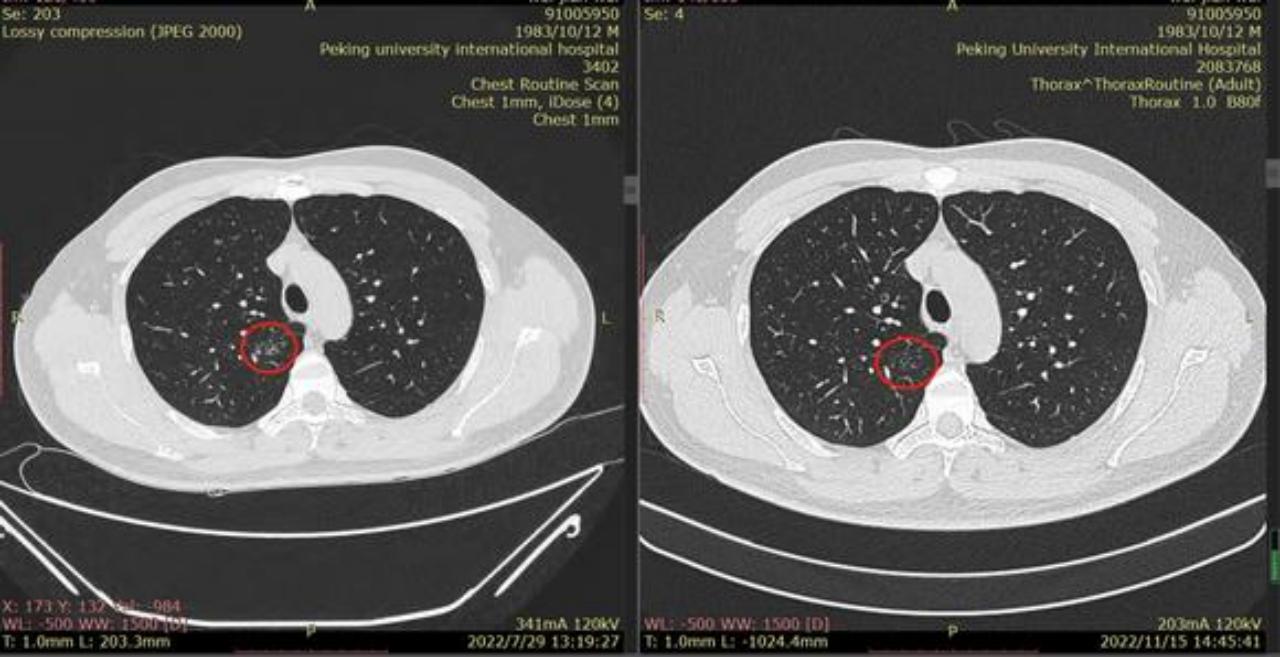

敬爱的戴主任,有个好消息跟您汇报,我老公的肺结节听您的建议服用拜复乐和夏枯草后缩小啦,7月29日的CT报告是1.9*1.1cm,同一家医院11月15日的CT报告是1.7*0.9cm,颜色也变浅了,您真是火眼金睛,华佗在世,我们的保护神!我们全家人的恩人!真心地谢谢您!

这是11月15日的CT图像与上次(7月29日)CT图像对比图:

再发一张:

辛苦主任,您看一下,结节虽然缩小了,还有1.7*0.9 CM,其他俩肺叶还有陈旧性病灶,应该继续服用拜复乐和夏枯草吗?8月份查过:男性肿标9项、过敏源检测(总IgE)、鳞状上皮细胞癌相关抗原、GM试验、隐球菌抗原、1,3-β-D葡聚糖 都是阴性,在正常范围内。就是结核感染T细胞还没查,您看是否需要查一下?主任辛苦您了,谢谢您!